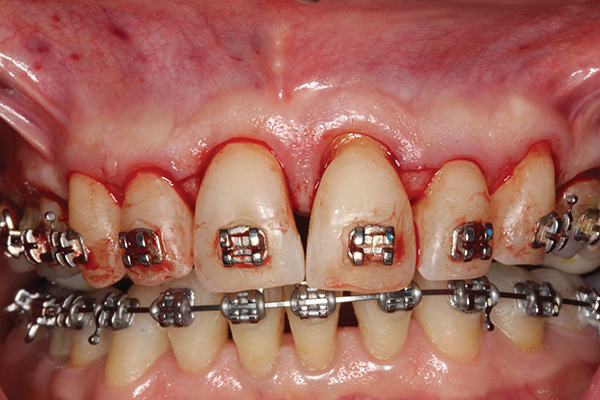

Fig 3. Corticotomy cuts performed.

Figure 3